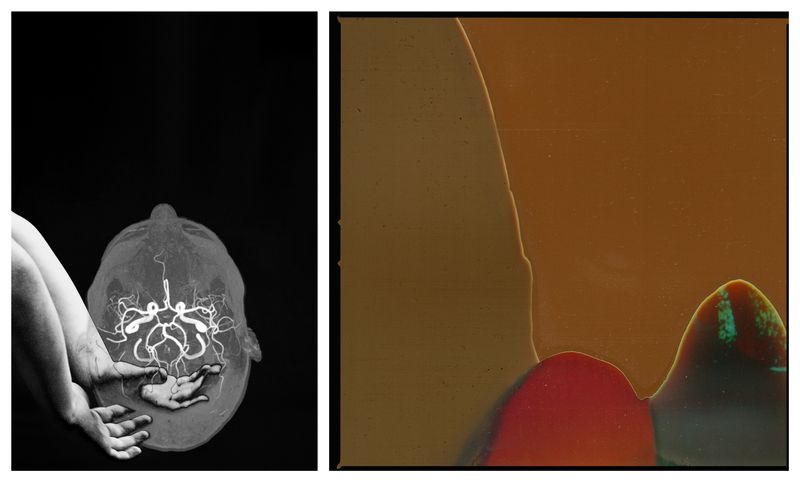

THIS DELICATE BRAINUnderstanding my neurodivergent mind gives me a deeper insight into my sensitivities.

BRAIN FOGAll roads lead to brain fog. Clarity is fleeting, like an elusive mirage shimmering just over the horizon, forever out of my reach.

PIECES OF MEMy Internal Timeline.

MOVABLE MOUNTAINSA reflection of my inner landscape, post-surgery.